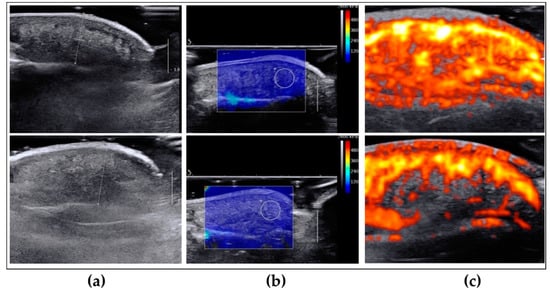

2.2. Evaluation of Morphological, Mechanical and Vascular Properties of Regenerated Fingertips

4.6. Power-Doppler and Elastography Assessment of Regenerated Fingertips